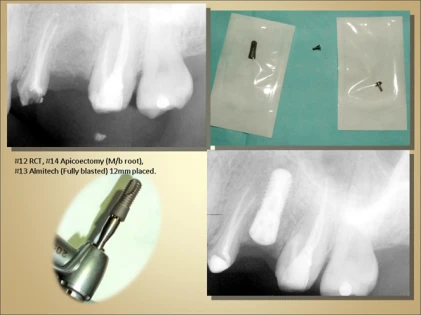

• Sizes: Implant diameter:3.3mm Platform 4.1mm, Length-10.0mm,12.0mm.